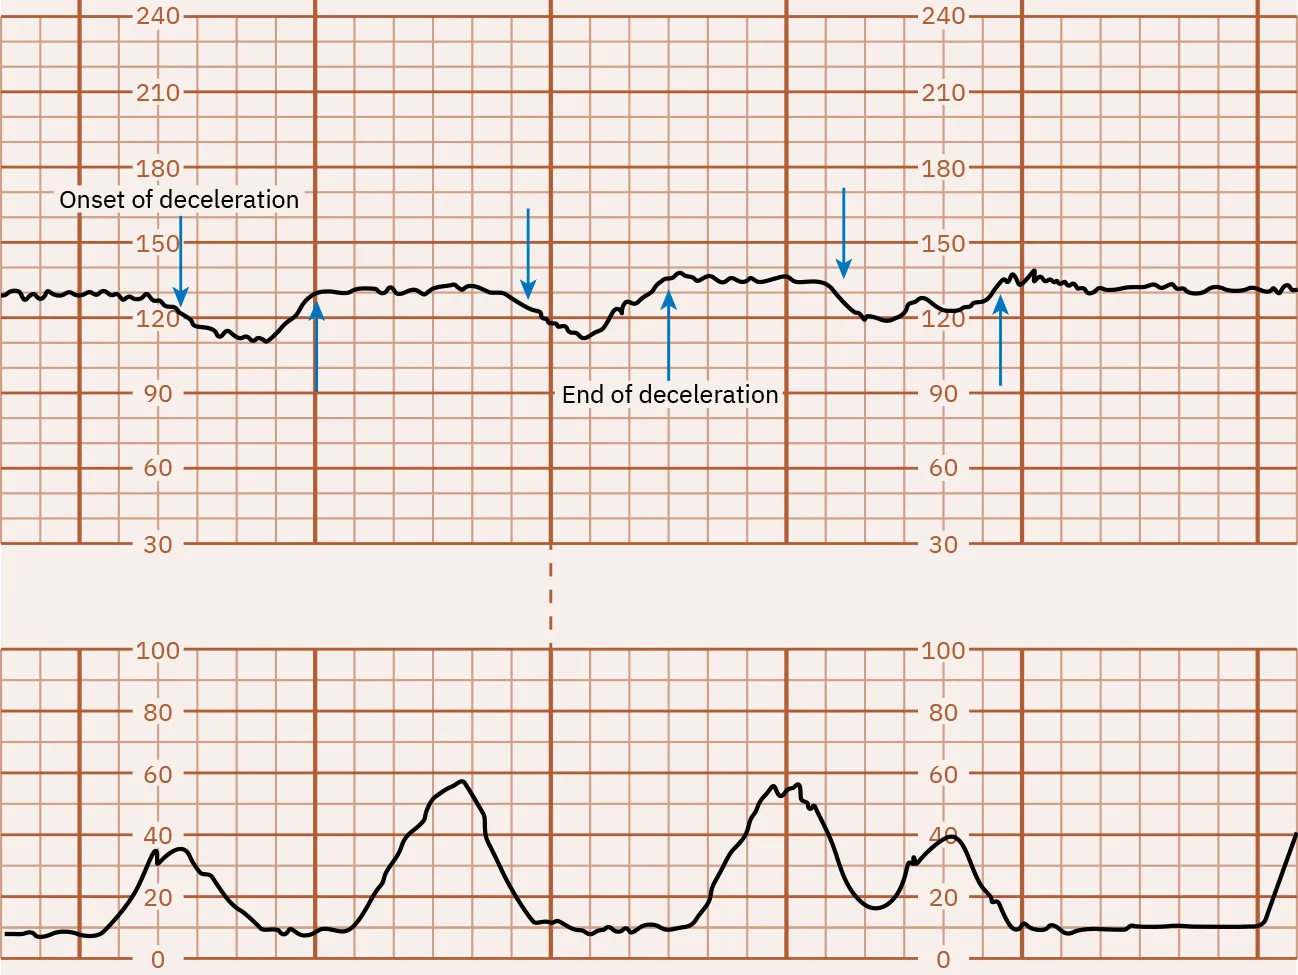

Variable Decelerations

Abrupt decelerations of the FHR of at least 15 bpm below the baseline that last at least 15 to 30 seconds are called variable decelerations. They do not typically appear in a pattern and vary in onset, depth, and duration. Variable decelerations are caused by compression of the umbilical cord. Cord compression can be caused by a fetal body part squeezing the cord against the wall of the uterus during a uterine contraction or movement related to the pregnant person or fetus. Because of this, the nurse will notice that variable decelerations may or may not occur in conjunction with uterine contractions. Variable decelerations may lead to fetal hypoxia, especially when they are repetitive for a prolonged period. Figure 16.13 shows a monitor tracing with an example of variable decelerations.

Fetal heart rate reading indicating variable decelerations.

Figure 16.13 Variable FHR Decelerations Variable decelerations appear with the contractions making a โ€œVโ€ or โ€œWโ€ shape. (attribution: Copyright Rice University, OpenStax, under CC BY 4.0 license)